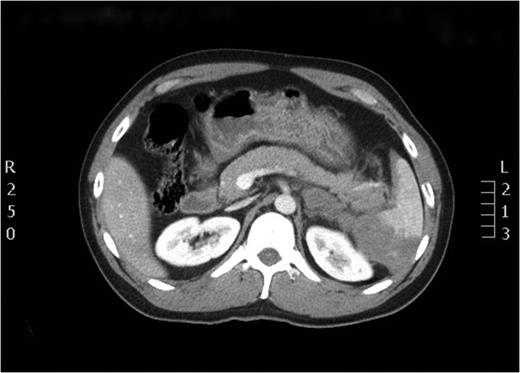

After the secondary survey, the patient was subjected to a computed tomography (CT) study, which showed a Grade IV splenic injury per the American Association for the Surgery of Trauma injury grading score with contrast extravasation (Fig. 1), a lower lobe contusion of the left lung, fractures of the IV and VI–XI ribs on the left side and bilateral iliac wing fractures. The pancreatic parenchyma was well perfused and homogenous in a portal venous phase CT-imaging (Fig. 2).

Axial view of the initial CT scan showing Grade IV splenic injury with contrast pooling in the peritoneal cavity.